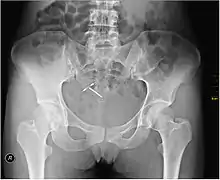

An intrauterine device (IUD), also known as intrauterine contraceptive device (IUCD or ICD) or coil,[3] is a small, often T-shaped birth control device that is inserted into the uterus to prevent pregnancy. IUDs are one form of long-acting reversible birth control (LARC).[4] One study found that female family planning providers choose LARC methods more often (41.7%) than the general public (12.1%).[5] Among birth control methods, IUDs, along with other contraceptive implants, result in the greatest satisfaction among users.[6]

IUDs are safe and effective in adolescents as well as those who have not previously had children.[6][7] Once an IUD is removed, even after long-term use, fertility returns to normal rapidly.[8] Copper devices have a failure rate of about 0.8% while hormonal (levonorgestrel) devices fail about 0.2% of the time within the first year of use.[9] In comparison, male sterilization and male condoms have a failure rate of about 0.15% and 15%, respectively.[10] Copper IUDs can also be used as emergency contraception within five days of unprotected sex.[11]

Although copper IUDs may increase menstrual bleeding and result in painful cramps,[12] hormonal IUDs may reduce menstrual bleeding or stop menstruation altogether.[13] However, women can have daily spotting for several months and it can take up to three months for there to be a 90% decrease in bleeding with hormonal IUDs.[14] Cramping can be treated with NSAIDs.[15] More serious potential complications include expulsion (2–5%) and rarely perforation of the uterus (less than 0.7%).[13][15] IUDs do not affect breastfeeding and can be inserted immediately after delivery.[13] They may also be used immediately after an abortion.[16][17]

Most copper IUDs have a T-shaped frame that is wound around with pure electrolytic copper wire and/or has copper collars (sleeves). The arms of the frame hold the IUD in place near the top of the uterus. The Paragard TCu 380a measures 32 mm (1.26") horizontally (top of the T), and 36 mm (1.42") vertically (leg of the T). Copper IUDs have a first year failure rate ranging from 0.1 to 2.2%.[34] They work by damaging sperm and disrupting their motility so that they are not able to join an egg. Specifically, copper acts as a spermicide within the uterus by increasing levels of copper ions, prostaglandins, and white blood cells within the uterine and tubal fluids.[12][35] The increased copper ions in the cervical mucus inhibit the sperm's motility and viability, preventing sperm from traveling through the cervical mucus, or destroying it as it passes through.[36] Copper can also alter the endometrial lining, and while studies show that while this alteration can prevent implantation of a fertilized egg ("blastocyst"), it cannot disrupt one that has already been implanted.[37]

Advantages of the copper IUD include its ability to provide emergency contraception up to five days after unprotected sex. It is the most effective form of emergency contraception available.[38] It works by preventing fertilization or implantation but does not affect already implanted embryos.[37] It contains no hormones, so it can be used while breastfeeding, and fertility returns quickly after removal.[39] Copper IUDs also last longer and are available in a wider range of sizes and shapes compared to hormonal IUDs.[14] Disadvantages include the possibility of heavier menstrual periods and more painful cramps.[12]